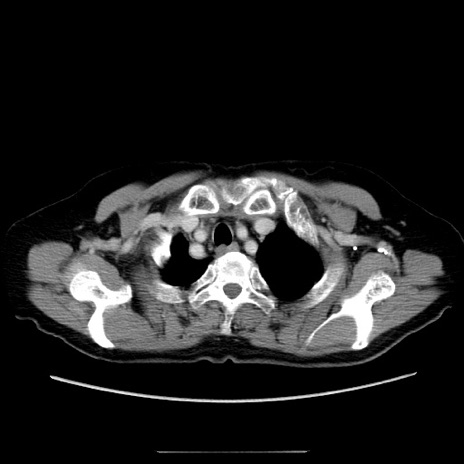

冠状断像

【症例】70歳代女性

【主訴】お腹が張る

【現病歴】1週間くらい前から腹部膨満の自覚あり。昨日夜から増悪したため、本日救急外来受診。

【身体所見】意識清明、BT 36.5℃、BP 165/106mmHg、HR 80bpm、SpO2 98%、腹部:膨満、軟、自発痛・圧痛なし、触診にて不快感あり、腸蠕動音:減弱

【データ】WBC 12600、CRP 1.04